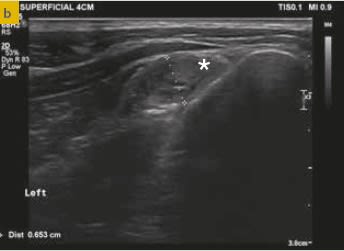

Editorial :  Edra. Miguel Solano Nicolás, Felipe de Vicente Collado, Alan Danielski, Stephen Kalff . 168 páginas . tapa dura. Ortopedia en pequeños animales. El miembro anterior se ha concebido como una obra práctica en la que se describen con detalle las técnicas quirúrgicas existentes, comunes y complejas, de las patologías más frecuentes del miembro anterior de perros y gatos, incluyendo desde la planificación de las intervenciones al posoperatorio. Los contenidos se acompañan de imágenes de gran calidad y más de 20 vídeos.